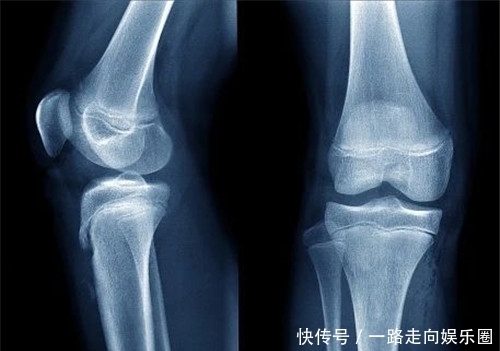

【 极端|生于侏儒,死于巨人,他是世界上唯一一个患有两种极端病症的人】尽管知道了病因,但是医生并没有能力消除雷纳尔身上的痛苦,由于医疗水平落后,肿瘤切除手术的成功率很低,所以医生也不敢为雷纳尔轻易做手术。可是,为了雷纳尔的生命,他还是切除了部分肿瘤,不敢再往里深入。后来,雷纳尔虽然停止了生长,但他却患上了糖尿病等并发症,最终1950年3月4日逝世,年仅51岁。经历了侏儒与巨人的雷纳尔,一辈子没有体验过正常人的生活,实在是令人叹惋。